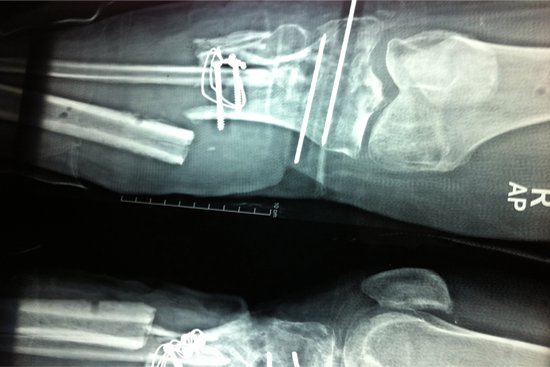

Tibialisation Of Fibula